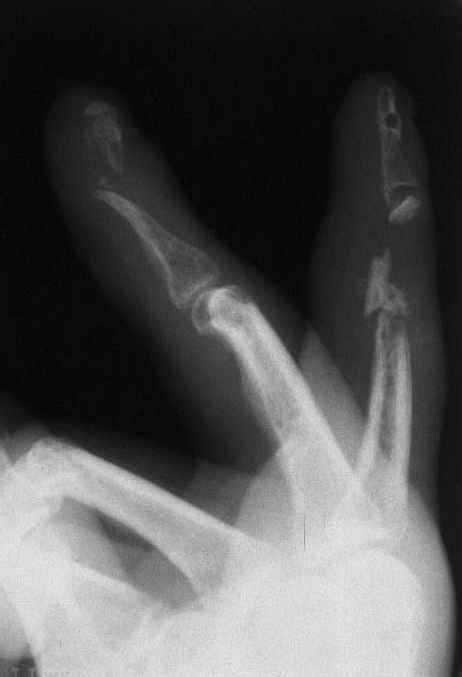

Уважаемые коллеги!На представленных снимках пальцы правой кисти мужчины 42 года через 3 месяца после травмы циркулярной пилой.

Качательные движения в проксимальном м/ф суставе 3 пальца. Нарушены все виды захвата, в которых принимают участие 2 и 3 пальцы. Кожные покровы с большими рубцами по тыльной и боковой поверхности пальцев. Ни магистральный кровоток, ни микроциркуляция специальными методами не оценивались. Косвенно о трофических нарушениях свидетельствует распространенный остеопороз дистальных фаланг и очаговый остеопороз основных фаланг и головок пястных костей, причиной которого возможно является и длительная иммобилизация в аппарате внешней фиксации. Чувствительных нарушений нет.

Планируем: 3 палец - открытый артродез дистального м/ф сустава с минимальной фиксацией спицей, тенолиз и разработка проксимального сустава (по этому пальцу в общем тактика ясна). 2 палец - обсуждается два варианта тактики:

1. Остеотомия основной фаланги, с последующей дистракцией в аппарате и удлинением последней до дистального м/ф сустава. Далее снова остеотомия - или неартроз, или эндопротез проксимального сустава, тенолиз. (Недостаток - будет потеряно время для восстановления функции сухожилий)

2. Костная пластика средней фаланги, одновременно тенолиз, артродез дистального м/ф сустава, разработка захватов. (Недостаток - опасаемся возможного некроза трансплантата вследствие ангиотрофических нарушений)Буду признателен за высказанные на форуме мнения по поводу пациента.